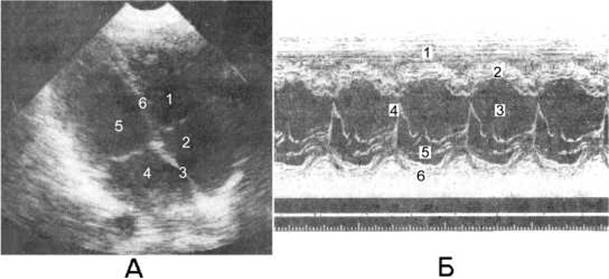

Мал. 135. Серце під час ультразвукового дослідження.

А - двовимірна ехокардіографія: 1 - правий шлуночок; 2 - праве передсердя; 3 - міжпередсердна перегородка; 4 - ліве передсердя; 5 - лівий шлуночок; 6 - міжшлуночкова перегородка;

Б - одновимірна ехокардіографія: 1 - правий шлуночок; 2 - міжшлуночкова перегородка; 3 - лівий шлуночок; 4 - передня стінка мітрального клапана; 5 - задня стінка мітрального клапана; 6 - задня стінка лівого шлуночка.

Ультразвукове дослідження серця (ехокардіографія) є інформативним, дешевим та безпечним методом дослідження серця у реальному часі і через це стало зараз основним методом променевого дослідження серця. Одновимірна ехокардіографія (М-метод) дозволяє отримати одновимірне зображення руху окремих структур серця протягом серцевого циклу. Ехограма має вигляд групи кривих, кожна з яких відповідає визначеній структурі серця: перикарду, стінкам шлуночка і передсердя, міжпередсердній і міжшлуночковій перегородкам, клапанам (мал. 135). Двовимірна (2D) ехокардіографія (В-метод) дозволяє вивчати анатомію, функцію, патологічні стани камер та клапанів серця, міжшлуночкової перегородки, скоротливості міокарда, патології перикарда. За допомогою доплер-ехокардіографії вивчають напрямок та швидкість потоків крові, що дозволяє виявляти дефекти перегородок серця і ураження його клапанів. За допомогою дуплексного методу ультразвукового дослідження, що об’єднує доплерографію та двовимірну сонографію (В-метод), оцінюють стан судин з аналізом кровотоку у будь-якому відділі судини.